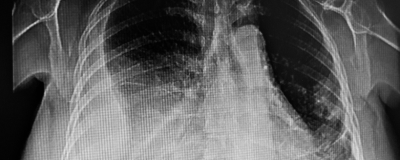

New study reviews incidence of pulmonary atelectasis after MRI sedation with propofol vs propofol-ketamine

Time to read: 02:01. In paediatric patients undergoing deep sedation for MRI, the propofol-ketamine combination significantly reduced post-sedation atelectasis, allowing a faster emergence time when compared with propofol alone.

Source: JAMA Network Open